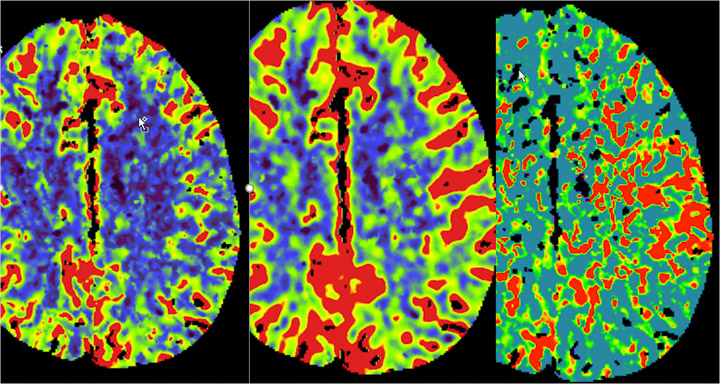

- Stroke (ischemic and hemorrhagic)

- Degenerative disorders of the brain

- 9 CT scanners including one dual energy CT.

- 8 clinical MR systems